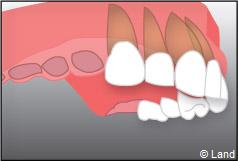

Exemple d’un implant unitaire pour remplacer une dent antérieure manquante.